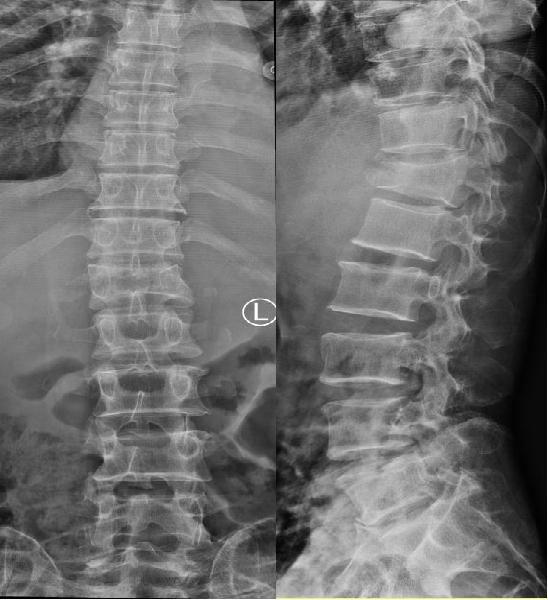

拍了 X 线为啥还要做 CT?MRI 又是查什么?

一、X 线:骨折筛查的 “侦察兵”

第一眼侦察:快速发现椎体形态改变,如椎体高度丢失、楔形变或后凸畸形。

初步定位:确定骨折椎体的位置,排除脊柱肿瘤等其他病变。

72 岁的王某腰背痛 3 天,X 线显示L1椎体 “楔形变”,高度丢失约 30%,初步诊断为 OVCF。但 X 线无法判断骨折是否新鲜,也看不清椎体后壁是否破裂,这时就需要 CT 和 MRI 出场了。